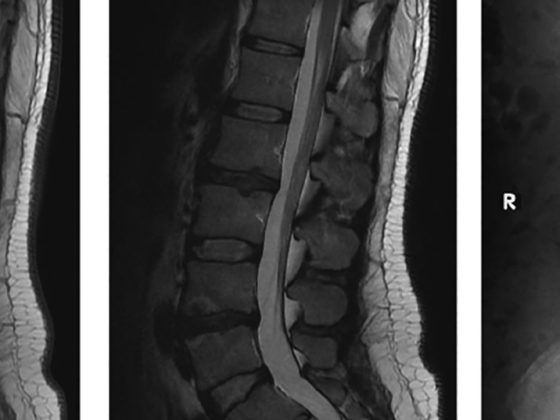

Lebenserwartung und Lebensqualität von ALS-Kranken lassen sich mit einer modernen Therapie verbessern. Der Wille des Patienten steht an oberster Stelle und muss immer wieder neu ermittelt werden. Neuigkeiten bei der medikamentösen Therapie gibt es nicht – Riluzol sollte früh begonnen werden. Zu Beginn der Erkrankung ist eine ausführliche Abklärung im stationären Rahmen einer neurologischen Klinik sinnvoll. Die Weiterbehandlung in spezialisierten Zentren während des Verlaufs der Erkrankung ist empfohlen.